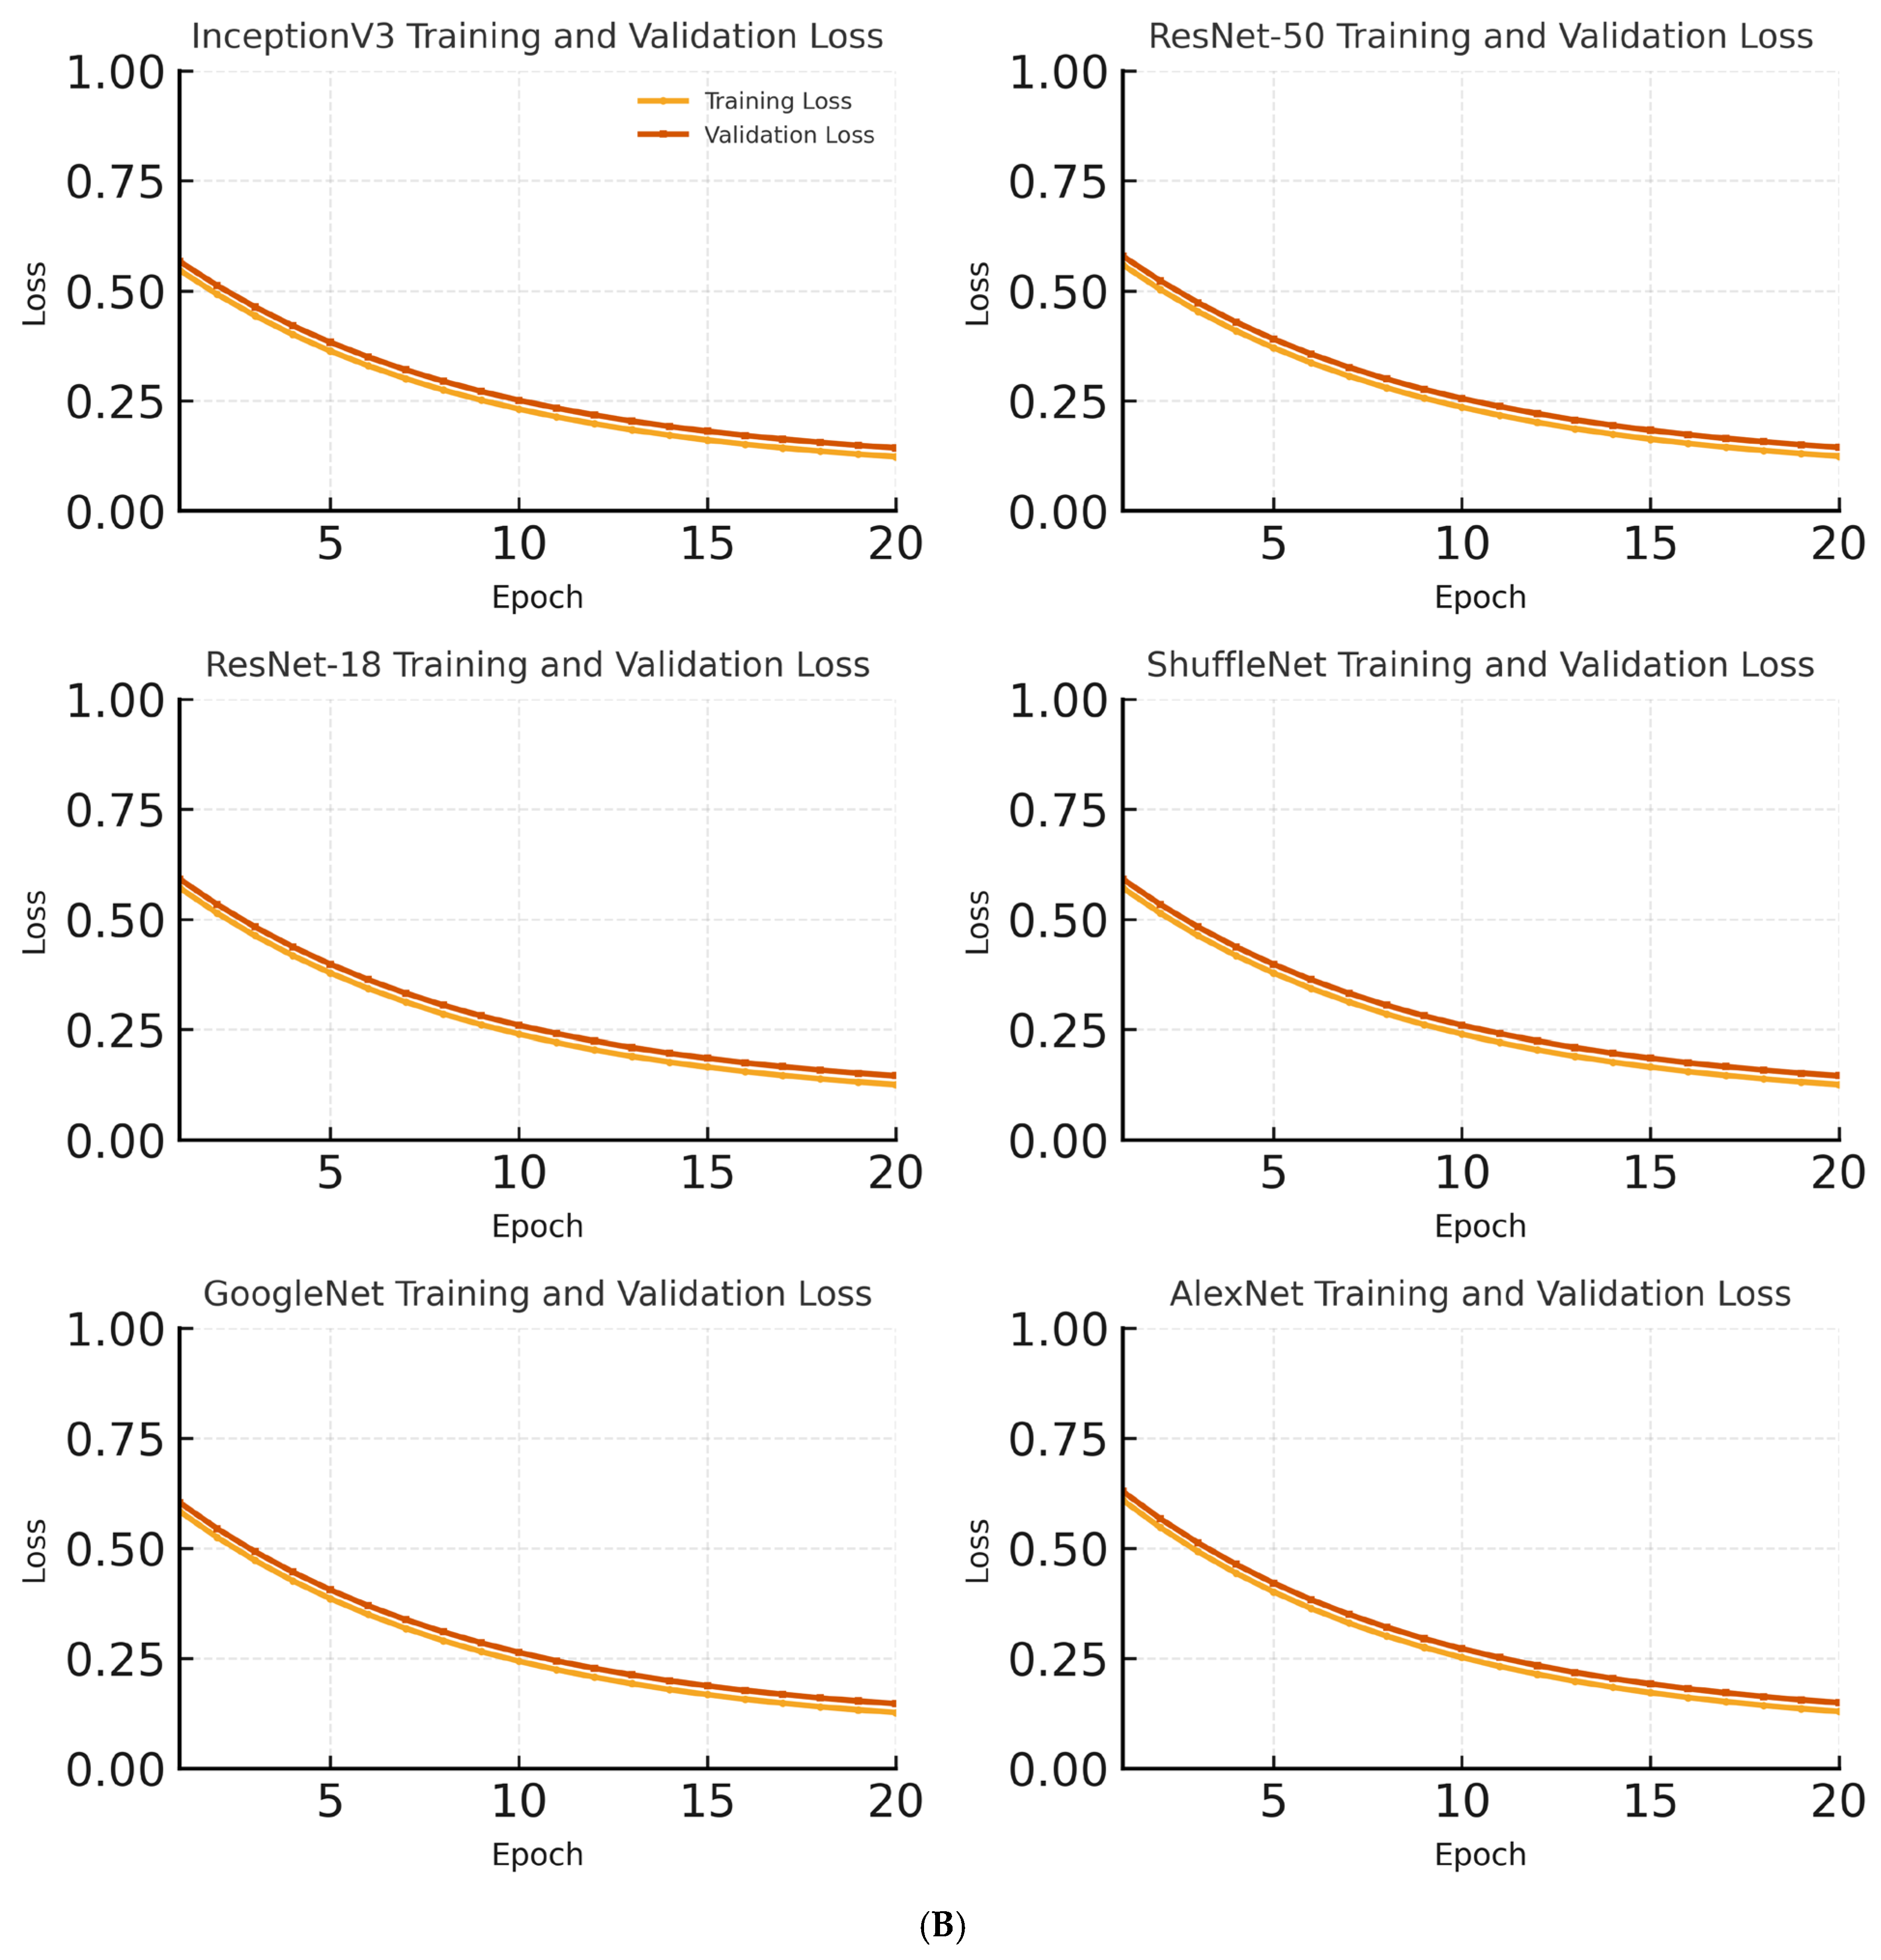

Figure 4. These matrices provide a visual overview of the classification performance for each model. In addition to accuracy, cross-entropy loss was recorded for both training and validation sets at each epoch to monitor overfitting and convergence during model training.

Figure 5 shows the changes in the training and validation accuracies of the InceptionV3, ResNet-18, and AlexNet models over epochs.

The training process was carried out for 20 epochs with a constant learning rate of 0.001 using the Stochastic Gradient Descent with Momentum (SGDM) optimizer. Early stopping was not employed because the validation and training accuracies progressed consistently without signs of overfitting.

In the InceptionV3 model, both the training and validation accuracies steadily increased across epochs. The training and validation accuracies reached 97% and 95%, respectively. The close progression of training and validation accuracies indicates that the model did not show a tendency for overfitting and has a high general success rate. Beyond the accuracy curves in

Figure 5A,

Figure 5B illustrates the corresponding training and validation loss. The validation loss followed the same trend as the accuracy, decreasing steadily and then plateauing without any signs of overfitting, even with the augmentation strategy in place. The validation loss curves were also analyzed in parallel with accuracy, and no significant overfitting was observed. The models demonstrated stable convergence, with training and validation loss decreasing and plateauing in a consistent manner, confirming that the augmentation strategy was effective in improving generalization without compromising performance.

In the ResNet-18 model, the training accuracy reached approximately 94%, whereas the validation accuracy was approximately 91% by the end of the epochs. The closeness of these accuracy values suggests that the model performed balanced learning on the dataset. However, compared to the InceptionV3 model, the slightly lower validation accuracy indicates that the ResNet-18 model has a more limited learning capacity.

For the AlexNet model, the training accuracy was approximately 90%, and the validation accuracy remained at 87%. The small gap between the training and validation accuracies indicates that overfitting was prevented. However, the overall accuracy levels being lower than the other models suggest that AlexNet’s simpler architecture limits its learning capacity.